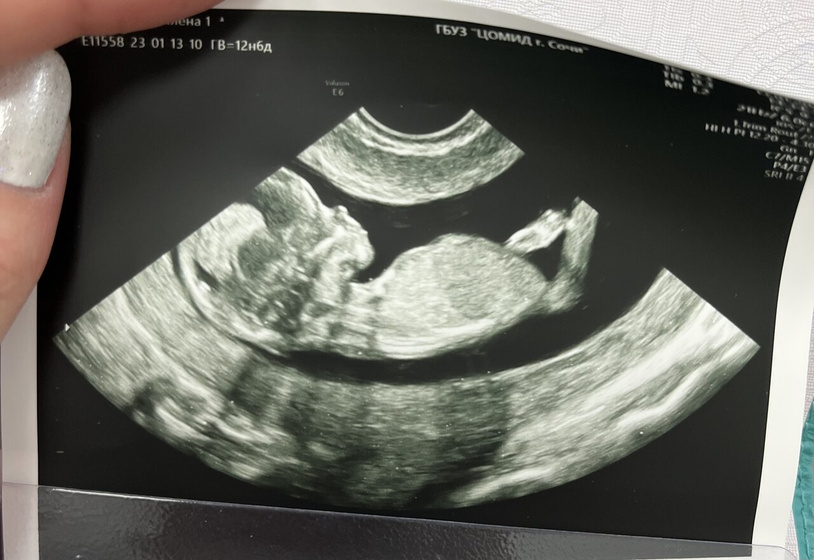

Сегодня была на первом скрининге ☺️Это так прекрасно увидеть через экран свое чудо?

С учетом того, что я не замечаю как проходит моя беременность, без признаков, с которыми многие мучаются(ну типа токсикоз). Сроки полностью у меня подтвердились 12,6 дней. Даже по некоторым 13 недель ровно. Слушала сердечко ? И зевали в камеру ?Сняла видео даже.

Сказали не видно, но предположили что девочка ?

Не видно было, но предположили что девочка ?

Как увидела фото, сразу подумала что девочка, миленькая крошка